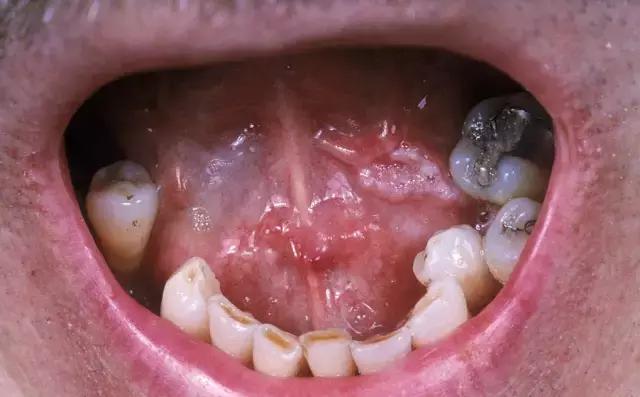

在临床上,很多患者是因为自觉“口腔溃疡”迁延不愈,疼痛难忍,才决定去医院检查,最终被确诊为舌癌。一般来讲,口腔溃疡发病比较短,10天左右即可治愈;因此如果舌缘、舌尖、舌背或者舌腹处的溃疡经过治疗,超过两周仍然无法愈合,就要提防癌变风险,需要进行病理检查。

舌癌癌前病变的表现有三种症状:白斑、红斑和扁平苔藓。如果发现口腔里长期有这样的症状表现,就要引起警惕。通常来讲,舌癌以老年人为高发群体,男性多于女性;但近年来,舌癌的年轻化趋势也很明显,二三十岁的患者不乏其人。

出现黏膜白斑,需要立即引起警惕

各种口腔问题引发的黏膜刺激和磨损,应尽早妥善处理

如果感觉口腔中某种不适感持续存在甚至逐渐加重——例如唾液分泌不正常地增加,或是咀嚼、吞咽时有疼痛或异物感,说话时感觉舌头运动功能受限,或是口腔环境的外观出现明显变化例如白斑、红斑、糜烂、隆起或者肉芽等,都要引起警惕,及时到医院检查。